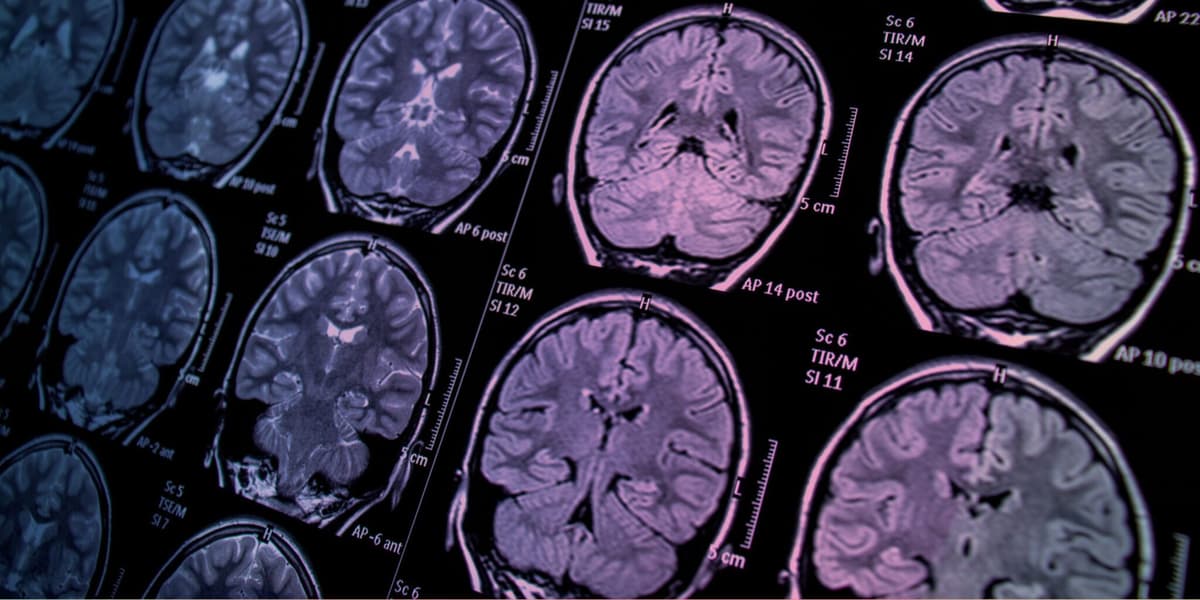

Protecting your brain health with proactive screening

Most strokes are preventable. Dr. Raman Palabindala identifies your specific risk factors, from undetected atrial fibrillation to uncontrolled blood pressure, and puts a prevention plan in place before a stroke can happen.

Through targeted screening, smart medication management, and practical lifestyle guidance, we help you protect the organ that matters most and maintain your independence for years to come.